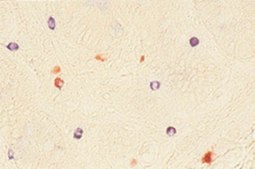

Anti-Tryptase Antibody, Mast Cell, clone G3

Tryptase is the most abundant secretory granule-derived serine proteinase contained in mast cells. Tryptase has recently been used as a marker for mast cell activation and is involved with allergic response. Tryptase may act as a mitogen for fibroblast lines. Elevated levels of serum tryptase occur in both anaphylactic and anaphylactoid reactions, but a negative test does not exclude anaphylaxis.

This Anti-Tryptase Antibody, Mast Cell, clone G3 is validated for use in FC, IH, WB for the detection of Tryptase.

Recognizes Mast cell tryptase. Will show reactivity to basophils but to a lesser degree.